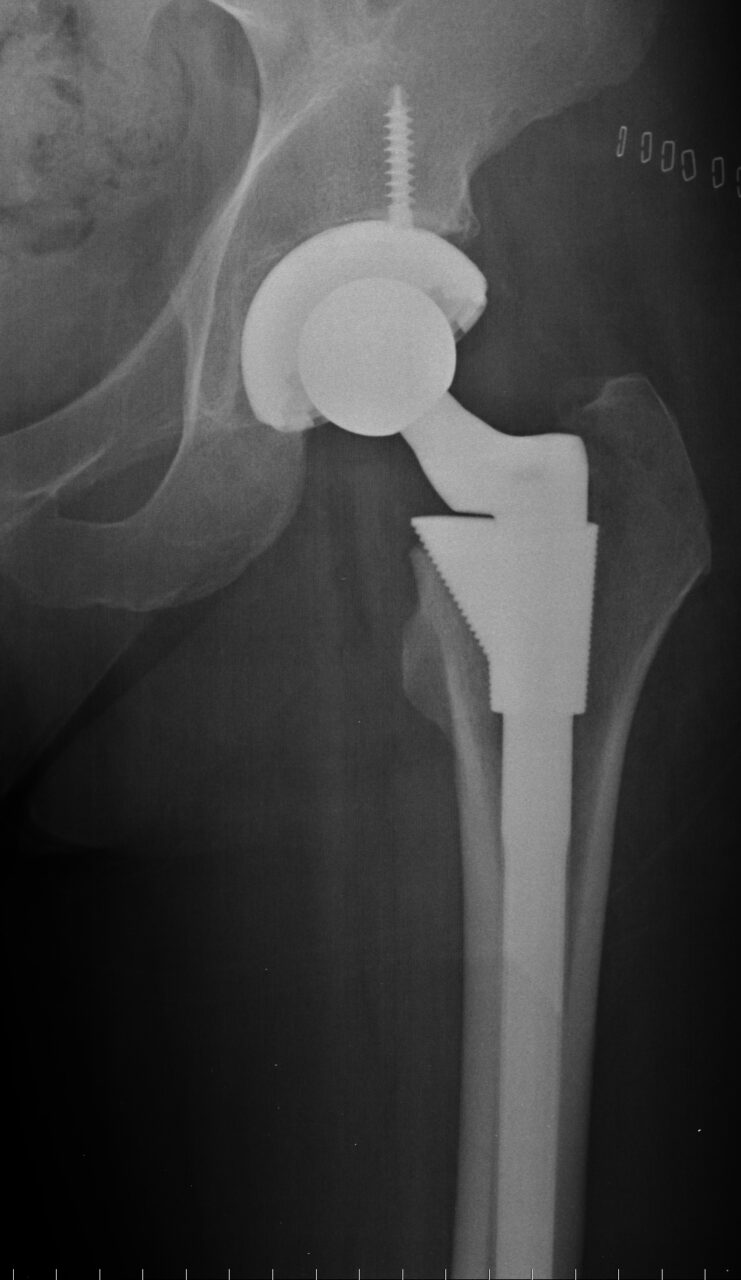

Joint Replacement

Rothman Orthopaedics' Joint Replacement Program is one of the nation's top joint replacement centers, performing more than 17,000 joint surgeries annually.

Because like all surgeries, joint replacement procedures do require some recovery time, they are normally only considered after all other non-surgical options have been discussed and/or attempted. Normally, joint surgery provides significant and wonderful results for the majority of patients. At Rothman Orthopaedic Institute, patients have the advantage of being seen by physicians who have actually helped develop and launch joint replacement techniques and who are considered to be well-renowned authorities on the topic of joint replacement

The joint replacement team at Rothman Orthopaedic Institute performs more than 9,000 surgeries every year. Each member of the team is specially trained, has extensive experience and is skilled to perform total joint replacements. Every physician that is a part of this outstanding team of doctors has undergone extensive subspecialty training during his/her residency and fellowship. This team is at the cutting edge of new research in the joint replacement field and Rothman physicians are actually responsible for training other orthopaedic surgeons through international lectures, webcasts, and surgical satellite simulcasts.

Is it right for you?

If you experience pain in any of your joints due to physical activities such as walking, running, and climbing stairs, it may be time to have a Rothman Orthopaedic Institute specialists diagnose your case. Joint replacement may be the answer for you. When simply sitting in a favorite chair or sleeping in your bed causes enough pain to wake you or make your life extremely uncomfortable, joint replacement may be able to get you back to an active lifestyle with less pain.